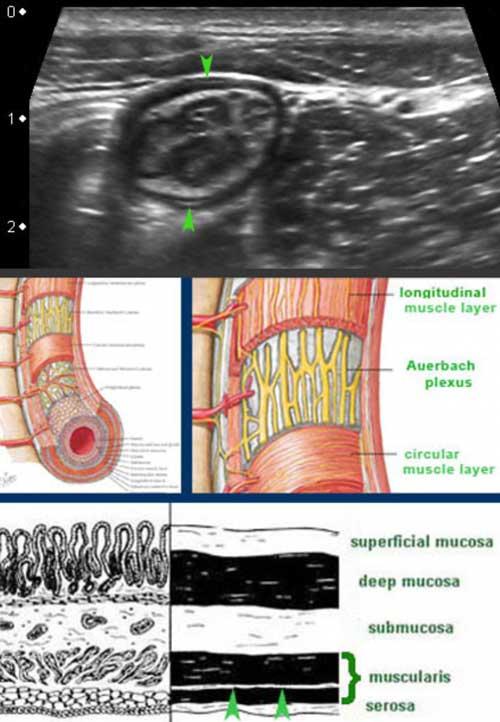

Muscularis

Lớp cơ có hồi âm thấp do cấu trúc mô cơ và dễ dàng nhận biết như một lớp đen ở phía ngoài.

Nó bao gồm hai lớp: lớp cơ vòng ở trong và lớp cơ dọc ở ngoài, phối hợp với nhau để tạo ra các chuyển động nhu động.

Hai lớp cơ này được ngăn cách bởi một lớp mô liên kết mỏng, chứa mô thần kinh của đám rối Auerbach.

Lớp mỏng này (đầu mũi tên) tăng âm trên siêu âm và có thể thấy ở ruột non của bệnh nhân gầy.

Mặc dù không có ý nghĩa lâm sàng, việc nhận diện riêng biệt đám rối Auerbach trên siêu âm cho thấy độ phân giải cao của siêu âm so với CT và MRI.

Lớp cơ của đại tràng khác với lớp cơ của ruột non.

Lớp cơ dọc chỉ giới hạn ở ba dải định hướng dọc, được gọi là dải cơ dọc kết tràng (teniae coli). Trong đại tràng rỗng, xẹp ở những bệnh nhân gầy, ba dải cơ dọc này (đầu mũi tên) thường có thể được xác định bằng siêu âm như một vùng dày lên cục bộ của lớp cơ, tách biệt với lớp cơ vòng bởi một đường tăng âm mỏng.

Trong hình ảnh theo chiều dọc này, chỉ xác định được một dải cơ dọc (đầu mũi tên).